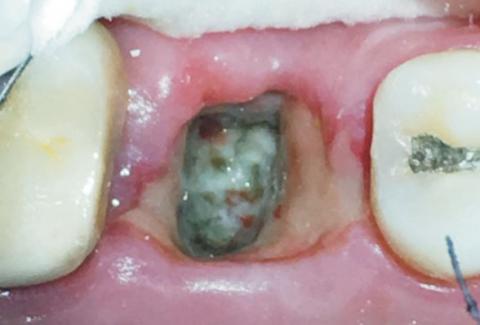

After a tooth extraction, many patients panic when they see white or yellowish material inside the socket on Day 2.

In most cases, this is completely normal healing.

But sometimes, it can signal a problem like dry socket.

On Day 1–3 after extraction, your body forms a protective healing layer.